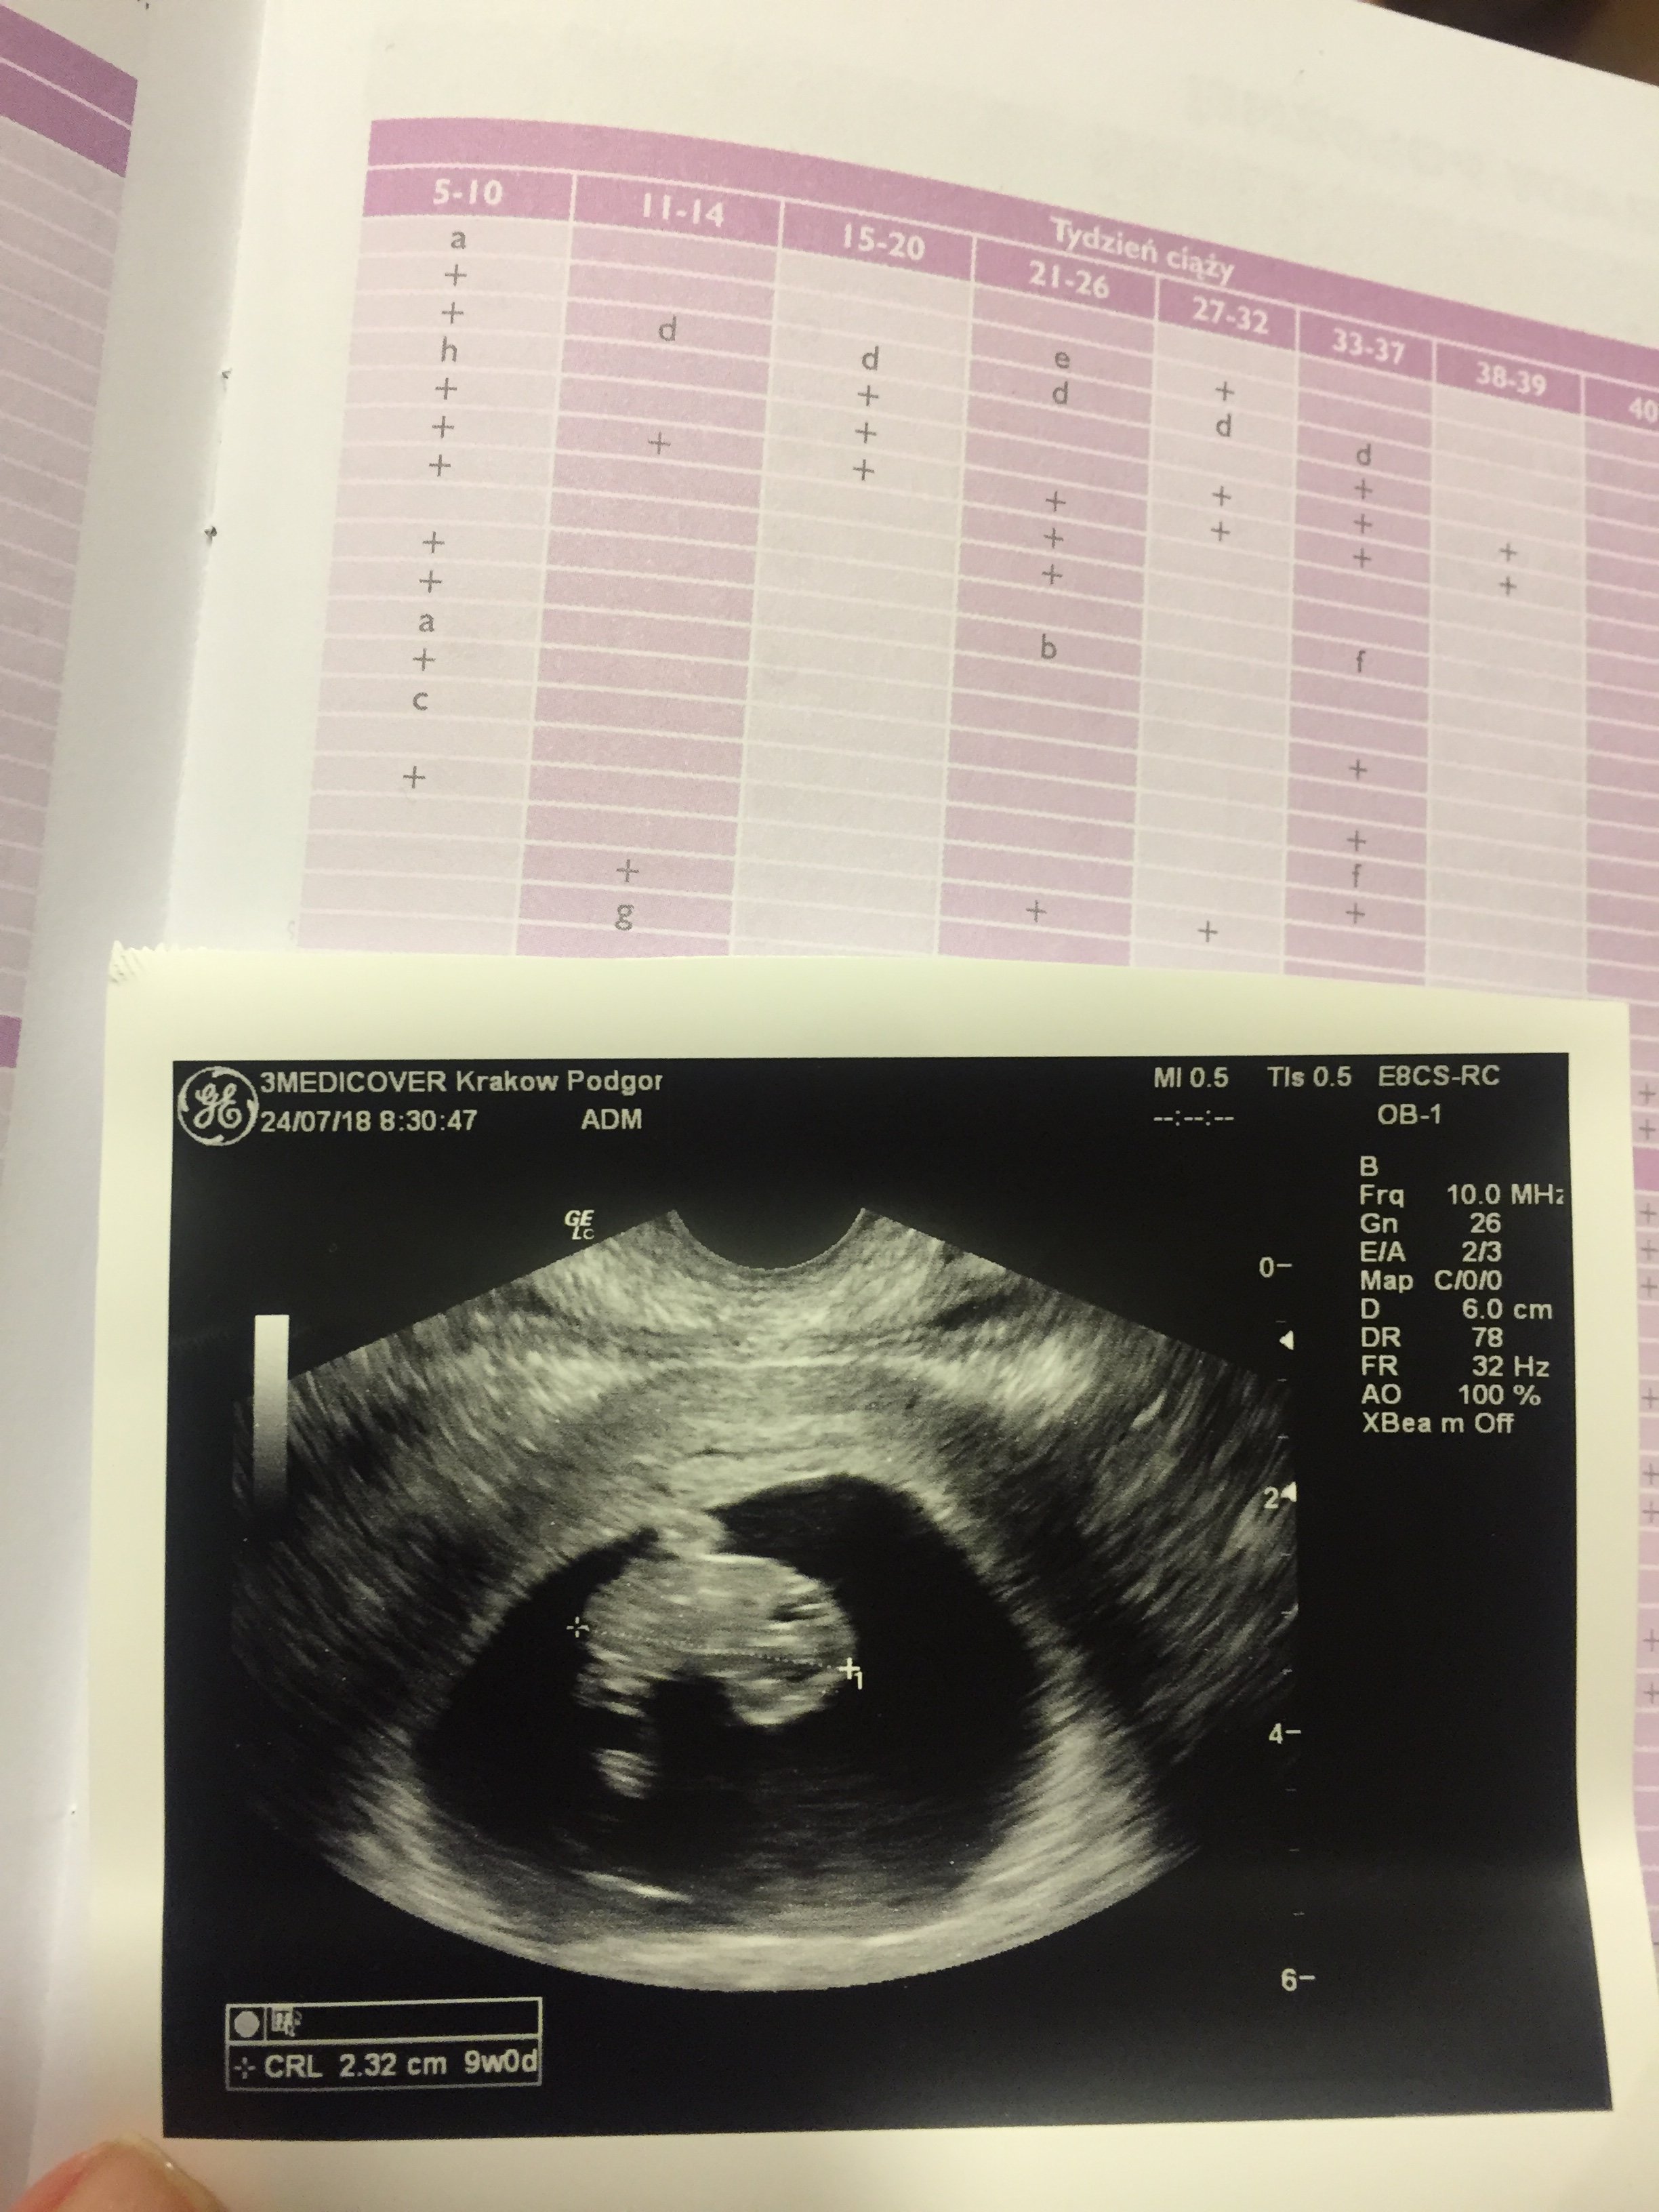

1. Genetyczne (inna nazwa: NT) - 11.0 - 13.6 (najlepiej wykonac miedzy 12-13 t.c.)

USG NT - bada sie przeziernosc karkowa, kosc nosowa, dokladne CRL, bicie serca itd. i min. dzieki tym parametrom spr. sie ewentualne wady plodu - trwa ok. 20-30 min. Wykrycie wad podczas samego badania USG wynosi ok. 75%